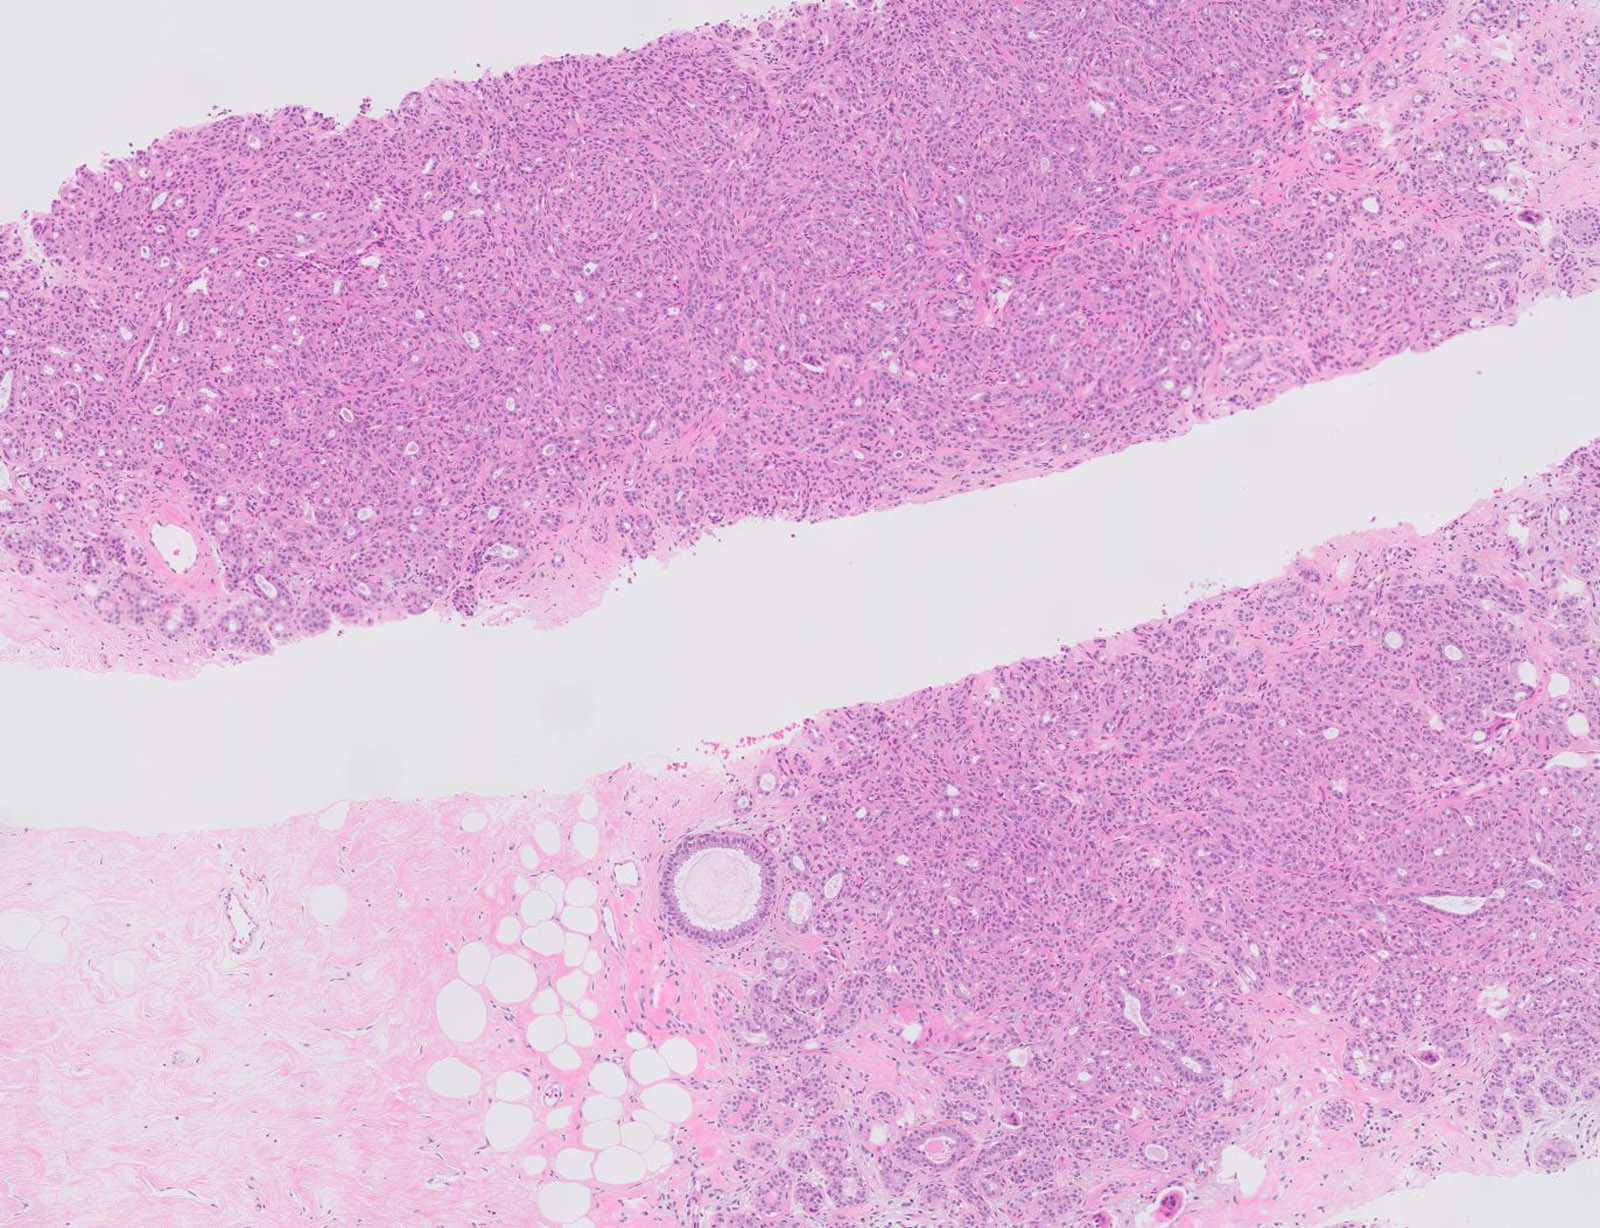

- Well defined borders

- Well defined borders

- Sparse fibrovascular stroma intervening tubules

- Small, uniform, closely packed round tubules (Clin Med Insights Pathol 2018;11:1179555718757499)

Microscopic (histologic) images

Contributed by Joshua J.X. Li, M.B.Ch.B. and Gary M. Tse, M.B.B.S.

Contributed by Jijgee Munkhdelger, M.D., Ph.D. and Andrey Bychkov, M.D., Ph.D.